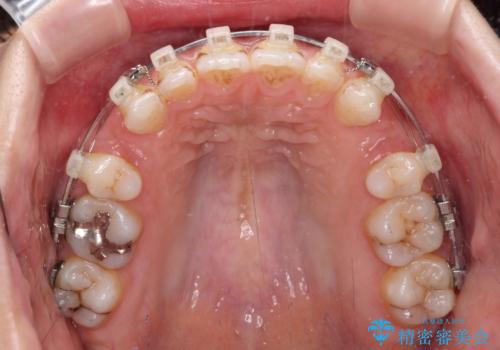

唇が閉じにくい ワイヤー装置での抜歯矯正

- 矯正装置

- クリアブラケット

- 唇が閉じにくく、上の前歯が下唇に当たって気になるとのことで来院された患者様です。

レントゲン写真での分析結果からは、抜歯矯正をするかどうか悩む境界線上でしたが、主訴が口元の突出感であったため、上下左右の第一小臼歯4本を抜歯して矯正治療を行うこととしました。